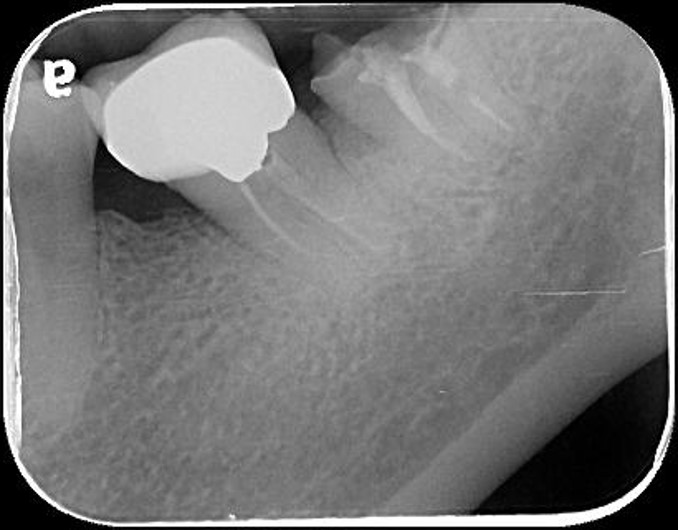

治療前,左下第二大臼齒假牙常脫落,前來求診

之前已根管治療